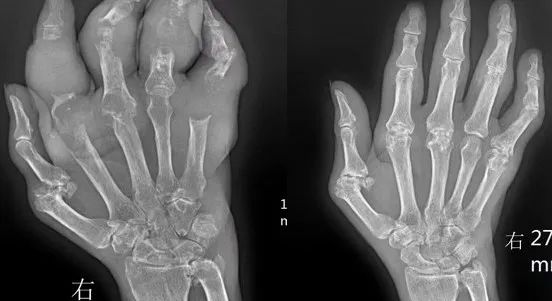

当尿酸水平达到目标范围后立即停药,尿酸代谢和排泄会逐步恢复原态,这是因为患者只是将血液中的尿酸降下来了,而皮下、肌肉、关节等各处沉积的尿酸盐结晶依然存在,这部分尿酸盐结晶又会溶解进血液中,使血尿酸水平回升。并且仅通过饮食控制只能减少外源性嘌呤摄入,不能改善肾脏对尿酸的排泄和内源性尿酸的生成。当尿酸水平达到目标值后,需要在专业医生的指导下,逐步减少降尿酸药物剂量,直到用最小剂量也能控制住血尿酸值在目标范围,长期维持一段时间后,再在医生的指导下尝试停药。如果患者有其他情况,如严重痛风石、高血压等,可能需要长期用药。